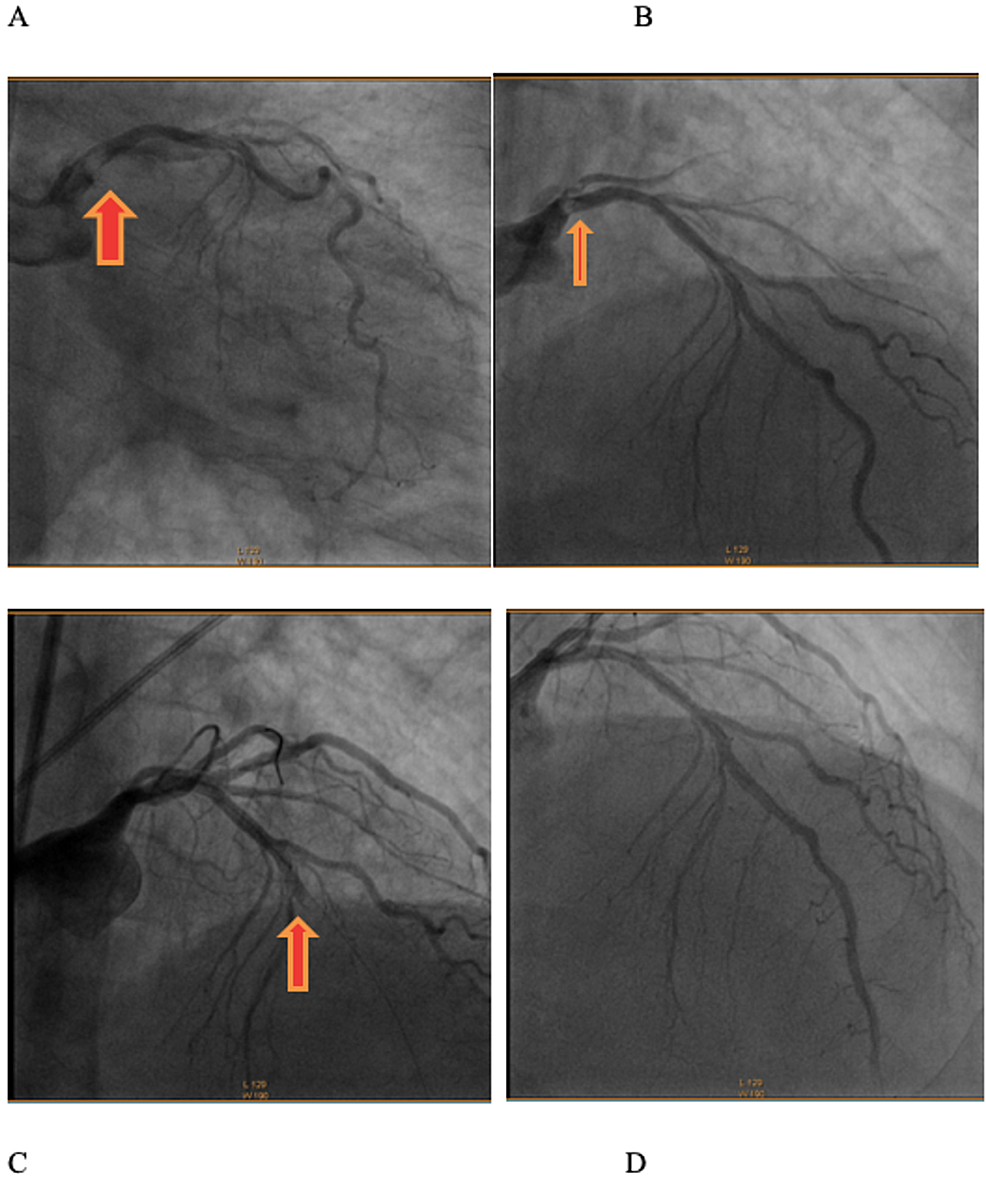

Myocardial Bridging In The Setting Of Dilated Myocardiopathy Cath Lab Digest

www.cathlabdigest.com